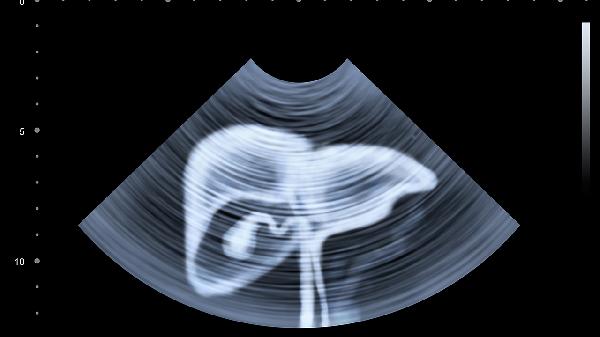

医生:肝癌并不是突然到来!上厕所时出现这4个症状,不要大意!

肝癌的发展往往是一个渐进的过程,早期症状可能并不明显,但身体会通过一些信号发出警.告。上厕所时的某些异常表现,可能就是肝脏在向你求.救。今天就来聊聊这些容易被忽视的警.示信号。